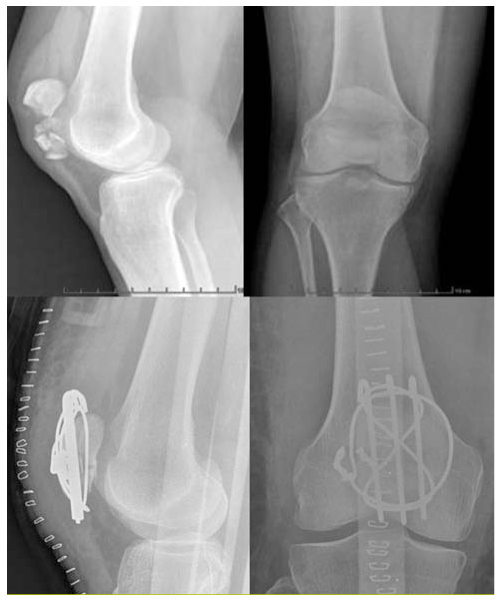

Fractures de la région du genou chez la personne âgée prise en charge

From www.revmed.ch

Fractures de la région du genou chez la personne âgée prise en charge Fracture Rotule Traitement La fracture de la rotule est une lésion osseuse fréquente suite à une chute sur le genou. On sait qu’elle va consolider sans qu’il y ait besoin de chirurgie. Découvrez les causes, les symptômes, le diagnostic et les traitements possibles d'une fracture de la rotule, un os du genou impliqué dans. Les chutes sur un sol dur. La fracture se. Fracture Rotule Traitement.